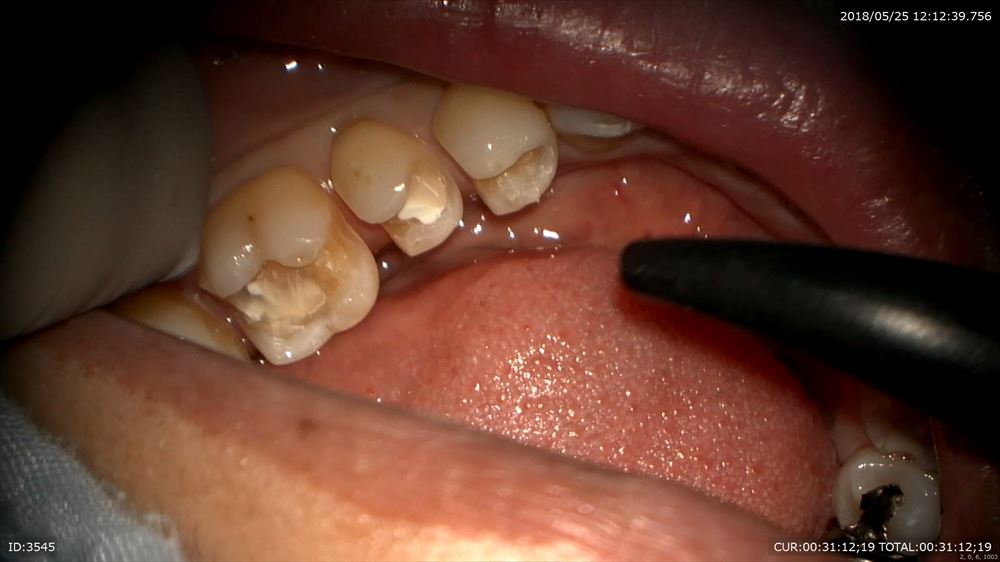

秋山勝彦先生にご指導のお蔭でこの様にマイクロスコープですべて直視下でできます。

6番の遠心見えます。

だから丁寧な形成が可能。両手が使えるから。

歯茎に1mmも触らずにできるから血もでません。無痛!!

このように当院では秋山勝彦先生が開発されたマイクロエンドスコーピックテクニックを駆使し治療しています。